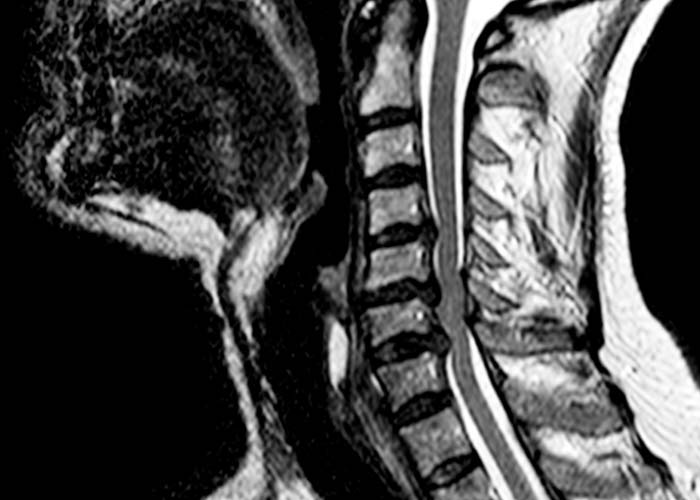

• Resonancia Magnética Cervical: voluminosas hernias discales cervicales C4-C5, C5-C6 y C6-C7 con estenosis del canal espinal central más acusado en C5-C6 y mielopatía cervical C5-C6.

Se trata de una afectación medular (mielopatía) por estenosis del canal medular en relación a la compresión de la médula por las hernias cervicales.

Debido a la afectación clínica neurológica requiere intervención quirúrgica de la columna cervical para descomprimir la médula espinal.